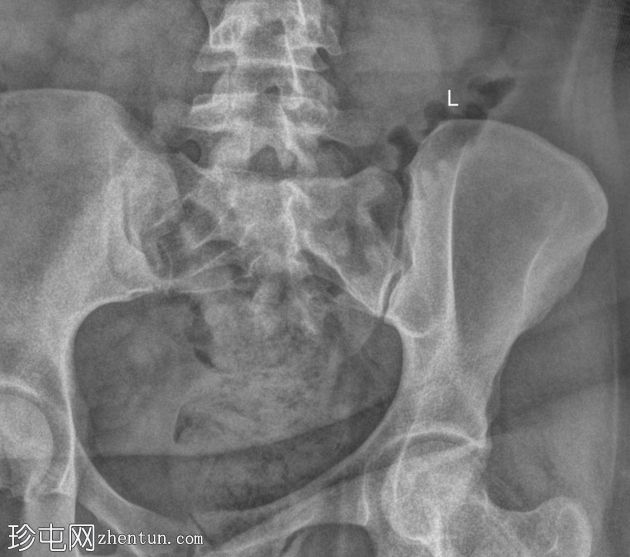

病例介绍

类

风湿

性关节炎伴腰痛。

患者资料

年龄:35岁

性别:女

X线片

正位

骶髂关节正位和斜位X线片显示正常。